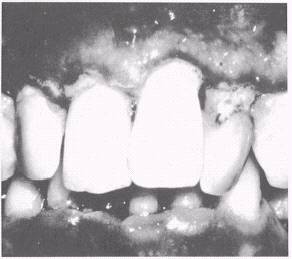

Marginal Gingivitis

Marginal gingivitis (fig. 5-7) is the most common type of gingival disease. Most frequently it is the result of poor oral hygiene and affects both the gingival margins and papilla. Chief irritants are food debris and plaque around the necks of the teeth, interproximal spaces, or overhanging margins of dental restorations. Occasionally, a localized inflamed condition may exist from a popcorn husk or toothbrush bristle. Early formation of calculus deposits can also form under the gingival sulcus (subgingival) on the facial and lingual surfaces of the upper and lower teeth. Calculus deposits can also be responsible for the occurrence of marginal gingivitis, and if left untreated, may proceed to destruction of the supporting structures (as in periodontitis).

Marginal gingivitis usually starts at the tips of the papillae and then extends to the gingival margins. Swelling, loss of stippling (orange peel texture of surface) of the attached gingiva, redness, easily retractable sulcus, and foremost, a tendency to bleed easily, are the main characteristics. This condition may be generalized (exist around all teeth), or it may be localized to one or two or a group of teeth.

Figure 5-7.\Marginal gingivitis.